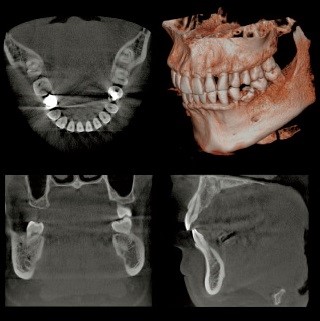

歯の状態や、歯を支える歯槽骨の状態、骨吸収の範囲と程度を検査します。

CT検査は立体的に歯槽骨の状態を診ることができるので、通常のレントゲンで顕著な骨吸収が診られた場合に撮影します。